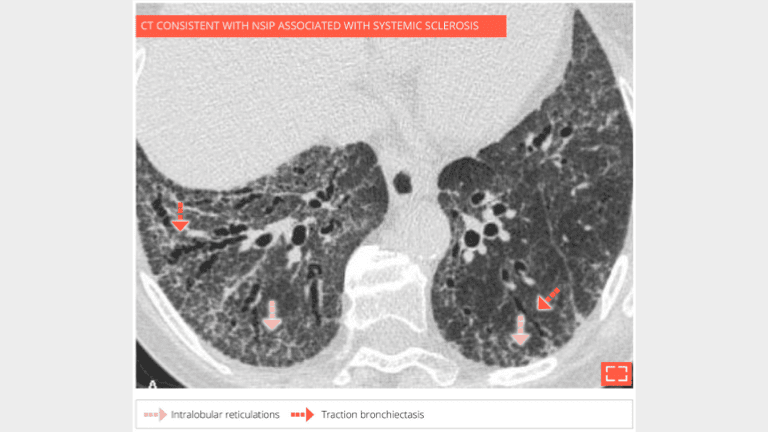

Diffuse ground-glass opacities in the lower posterior lungs with intralobular reticulations and traction bronchiectasis, no honeycombing.

Marked intralobular reticulations in the 2 lung bases without honeycombing. Note the relative lung savings immediately under pleura, pointing to a NSIP.